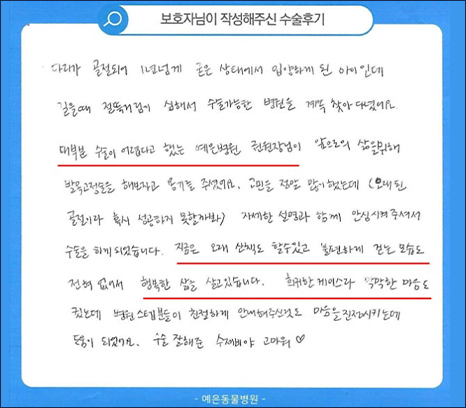

치료 후기

다리가 골절되어 1년 넘게 굳은 상태에서 입양하게 된 아이인데 걸을 때 절뚝거림이 심해서

수술 가능한 병원을 계속 찾아 다녔어요. 대부분 수술이 어렵다고 했는데

예은병원 권원장님이 앞으로의 삶을 위해 발목고정술을 해보자고 용기를 주셨어요.

고민을 정말 많이 했는데 (오래 된 골절이라 혹시 성공하지 못할까봐) 자세한 설명과 함께

안심시켜주셔서 수술을 하게 되었습니다. 지금은 오래 산책도 할 수 있고 불편하게 걷는 모습도

전혀 없어서 행복한 삶을 살고있습니다. 희귀한 케이스라 막막한 마음도 컸는데 병원 스텝분들이

친절하게 안내해주신 것도 마음을 진정시키는데 도움이 되었어요. 수술 잘해준 수제비야 고마워